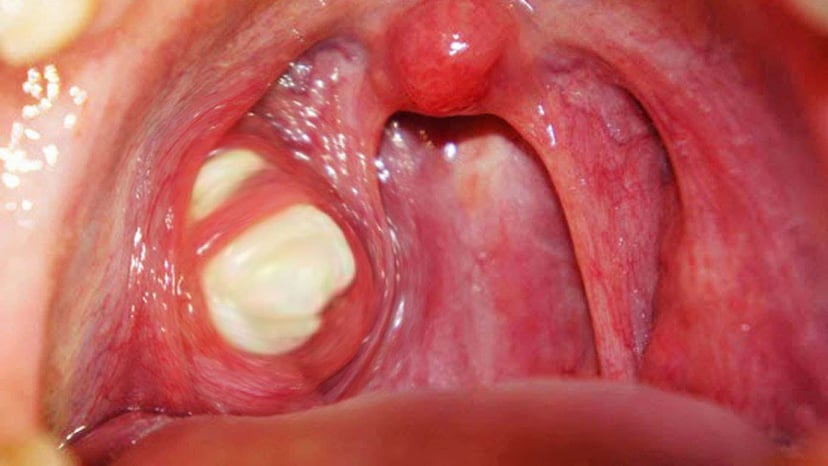

Viêm Amidan hốc mủ có những khối mủ bã đậu màu trắng và có mùi hôi

– Khi quan sát sẽ thấy hốc Amidan có mủ màu trắng hoặc xanh lấm tấm trong miệng.

– Amidan bị sưng đỏ, phình to và dịch màu trắng trên bề mắt.